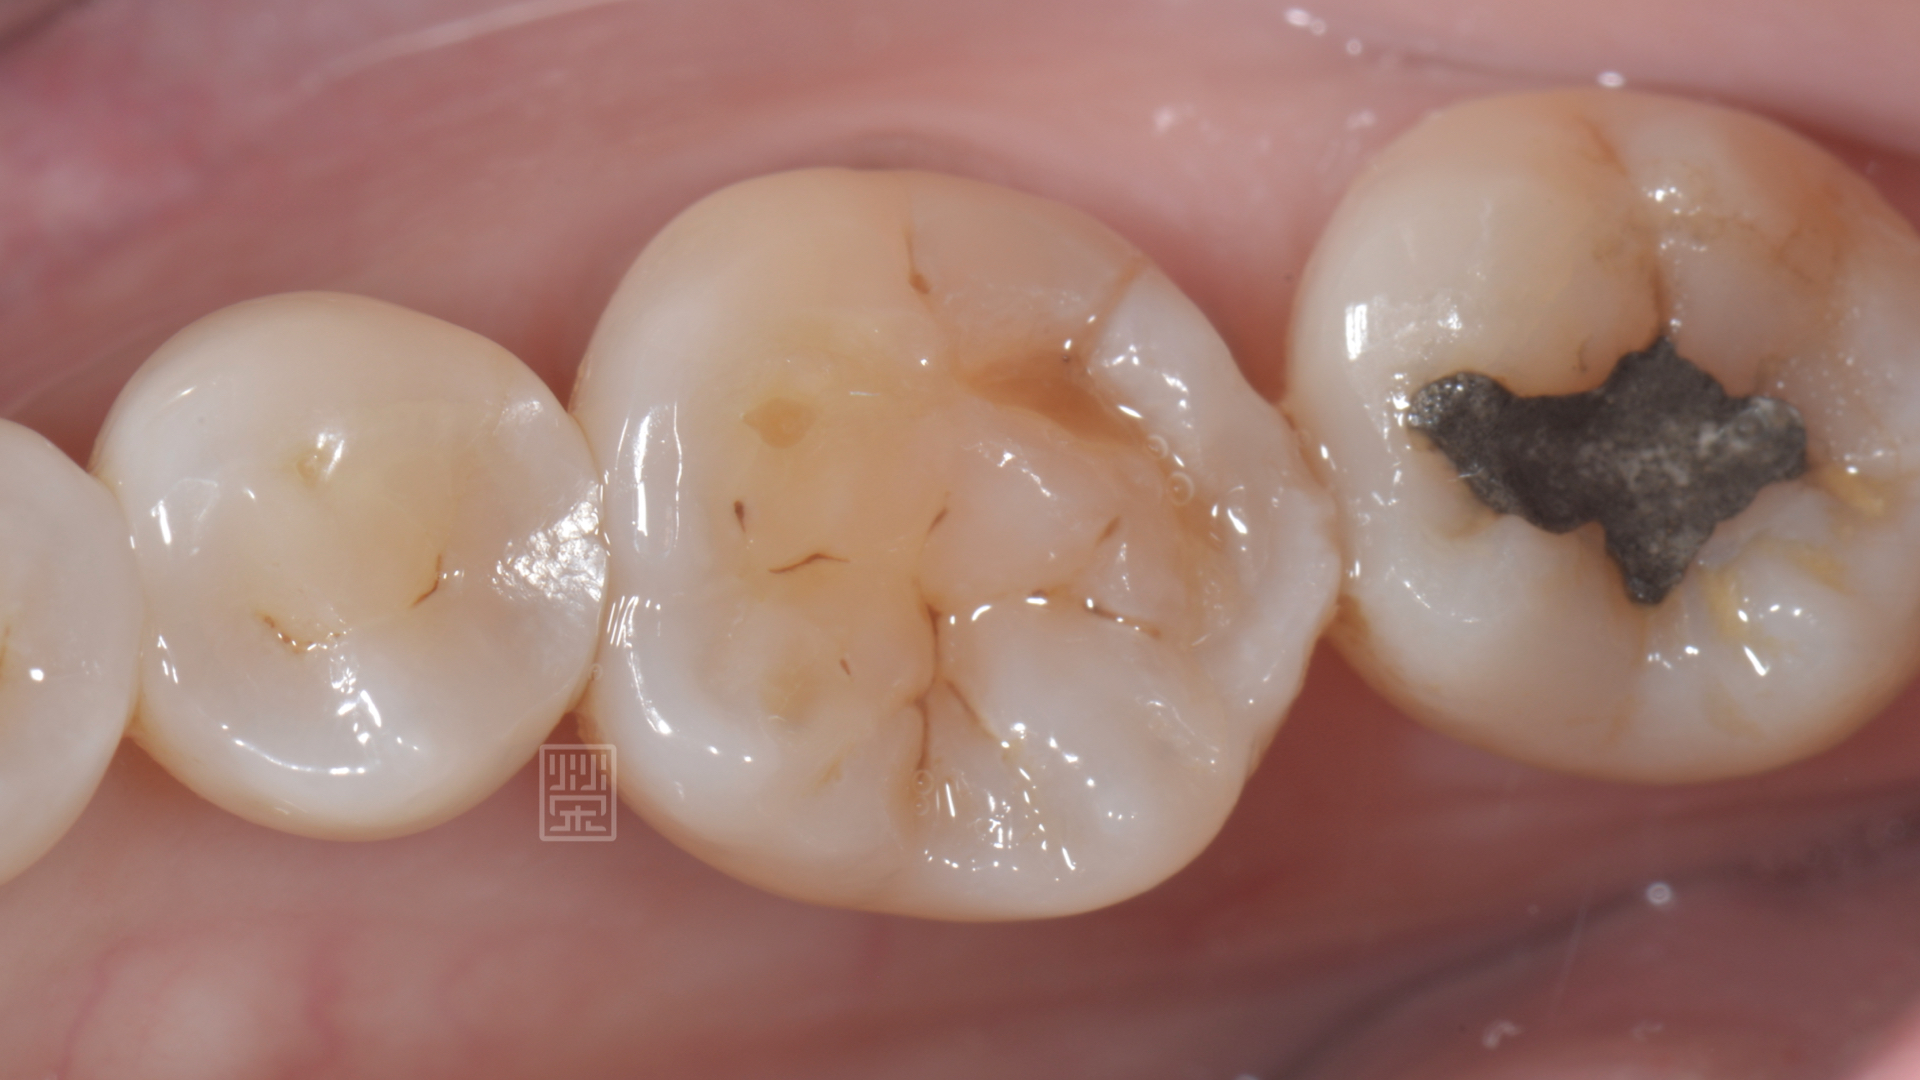

咬合面耗損